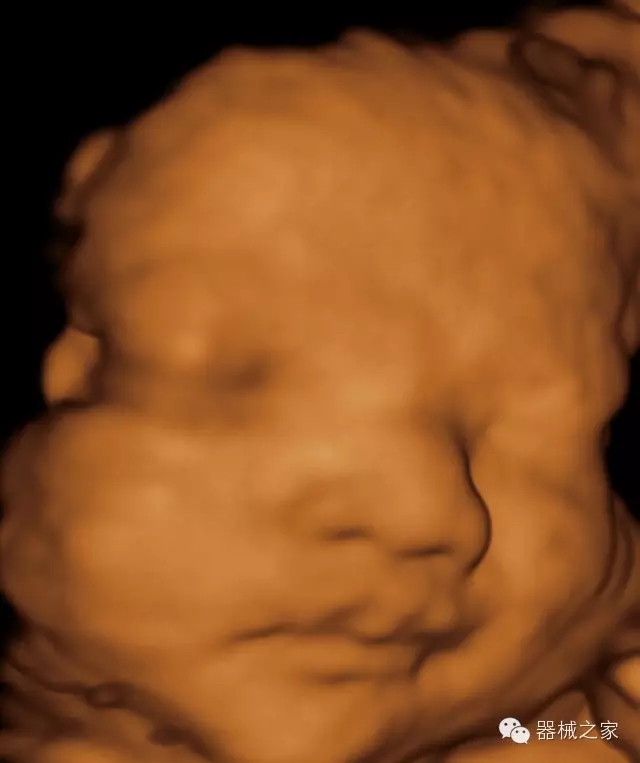

臨床圖片賞析

·完整的3D/4D臨床應(yīng)用,STIC, MCUT 和Auto NT等滿足產(chǎn)科所有應(yīng)用;

·更高的HQ羊膜腔鏡成像技術(shù)精細(xì)觀察每一個(gè)暗區(qū)細(xì)節(jié);

·智能的觸摸屏界面,能任意角度方位旋轉(zhuǎn)3D圖像,以及注釋快速標(biāo)記,提供直觀與便捷的操作,提高了工作效率;